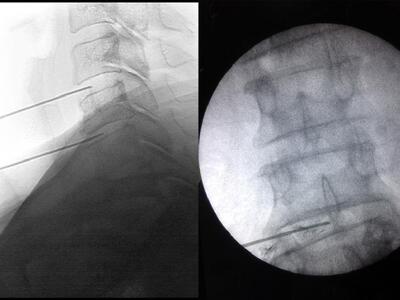

Η διαδικασία είναι σχετικά απλή και περιλαμβάνει τη λήψη ποσότητας μερικών κυβικών εκατοστών αίματος από το ασθενή το οποίο στη συνέχεια φυγοκεντρείται για μερικά λεπτά. Το πλάσμα πλούσιο σε αιμοπετάλια που προκύπτει από τη φυγοκέντριση εισάγεται υπό τοπική αναισθησία ή ήπια καταστολή και υπό συνεχή ακτινοσκοπική παρακολούθηση για απόλυτη ακρίβεια με ένεση στους πάσχοντες μεσοσπονδύλιους δίσκους. Για τη σωστή επιλογή του ή των δίσκων όπου θα γίνει η έγχυση του PRP εκτός από τη μαγνητική τομογραφία της ΟΜΣΣ προηγείται (την ίδια ημέρα της έγχυσης) διαγνωστική δισκογραφία. Η όλη διαδικασία διαρκεί περίπου μία με δύο ώρες, ολοκληρώνεται στον ίδιο χρόνο και δεν απαιτείται νοσηλεία ή ειδική προφύλαξη μετά την έγχυση. Επιπλέον, δεν υπάρχει κίνδυνος αλλεργίας ή υπερευαισθησίας μιας και χρησιμοποιείται αποκλειστικά και μόνο το ίδιο το αίμα του ασθενούς, ενώ η πιο συχνή ήπια παρενέργεια της ενδοδισκικής PRP ένεσης είναι η παροδική αύξηση του πόνου λόγω της έγχυσης υγρού στο μεσοσπονδύλιο δίσκο. Τα ευεργετικά αποτελέσματα της έγχυσης γίνονται αντιληπτά από την πρώτη κιόλας εβδομάδα, ενώ η βελτίωση συνεχίζεται και μεγιστοποιείται την 6η κατά μέσο όρο εβδομάδα μετά την έγχυση. Αντενδείξεις της μεθόδου αποτελούν η παρουσία μικροβιακής επιμόλυνσης, η αντιπηκτική αγωγή και οι διαταραχές της πηκτικότητας του αίματος του ασθενούς.